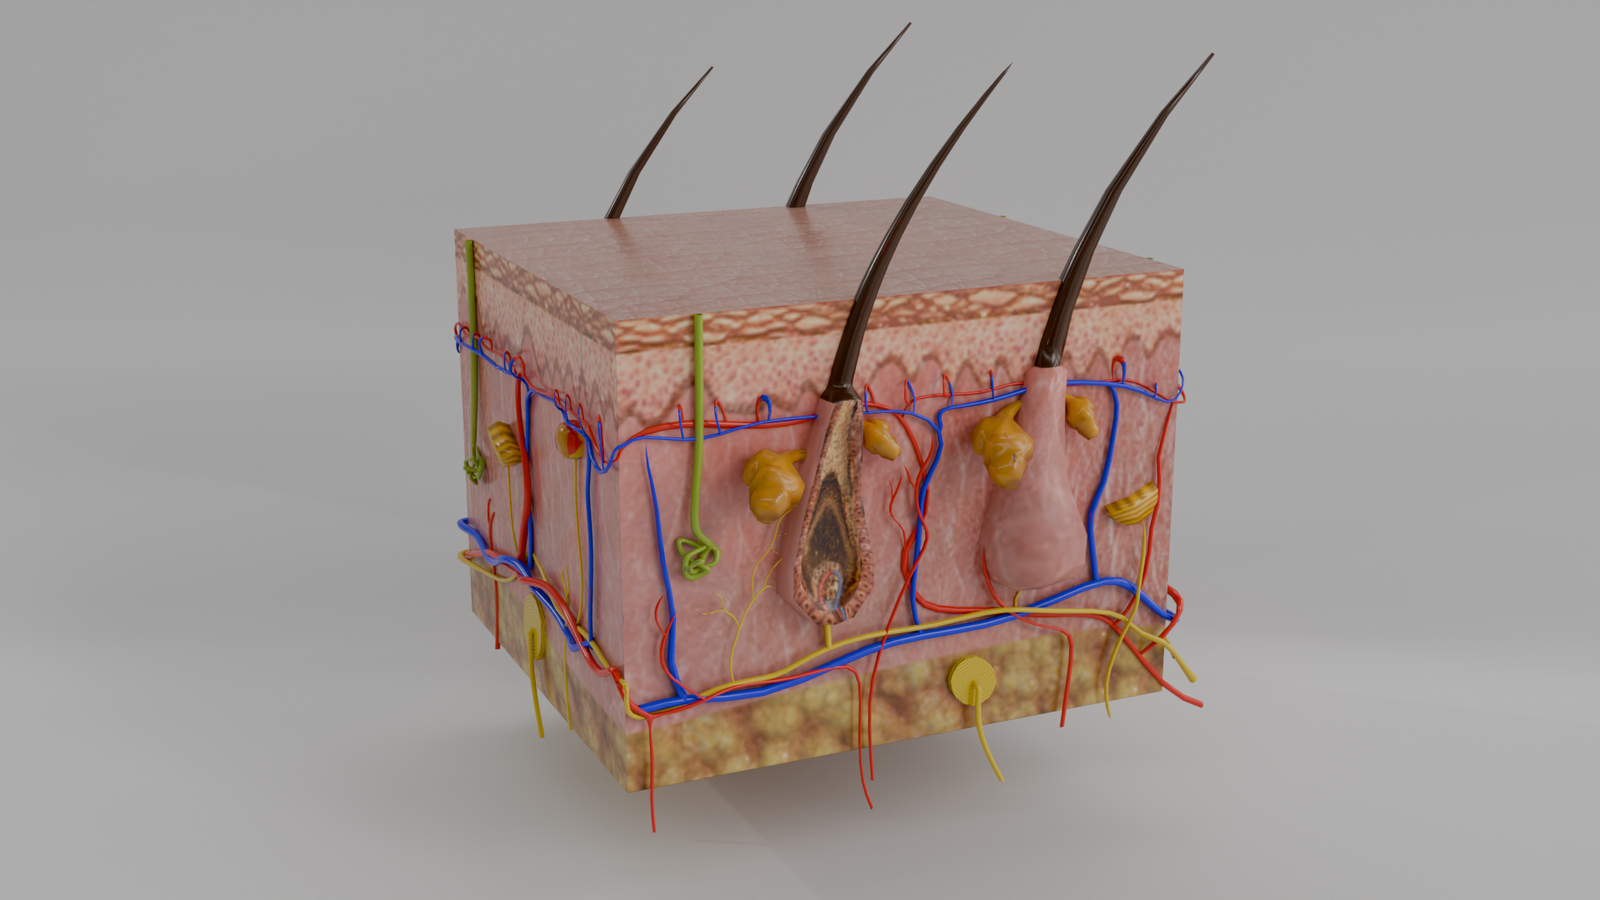

Piel

Modelo 3D educativo